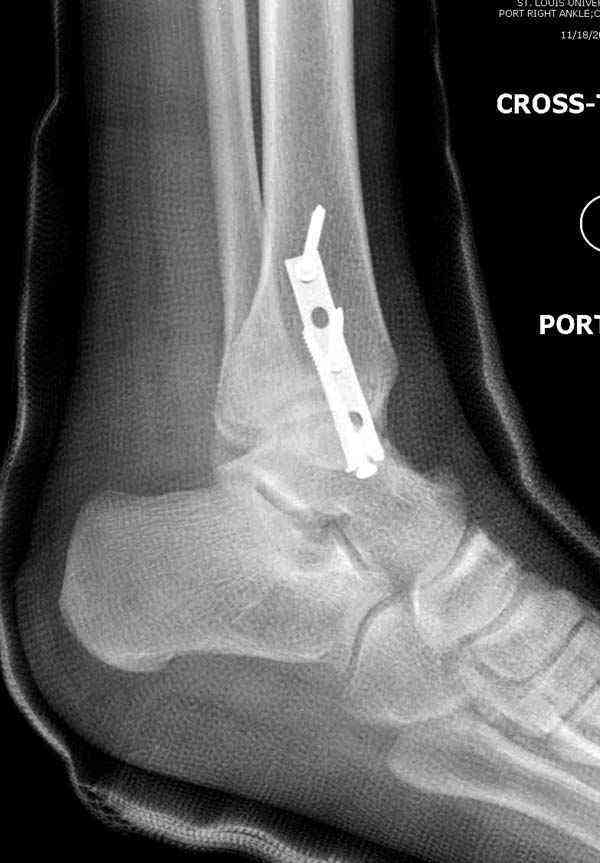

Случай прошлого года:пациентка-молодая ,крупная женщина ,30лет.Травма в начале апреля 2009г-пронационный перелом лодыжек с подвывихом стопы.Ко мне обратилась через 35 дней,прооперирована 22.05.2009г.Внутренняя лодыжка фиксирована по Веберу,наружная реконструктивной пластиной с наложением болта-стяжки.Иммобилизация "сапожок" в течении месяца,затем пригипсовано "стремя".Гипс снят 10.07.2009г

Достаточно быстрое восстановление функции.В октябре 2009г-почувствовала боль,в области рубца над гайкой открылся свищ.На Р-граммах-консолидация переломов и смещение гайки по стяжке.10.11.2009г-конструкции удалены,санация,заживление ран.В настоящее время пациентку ничего не беспокоит.На операции-раскручивание гайки-болталась на конце стяжки.Вопросы:какой механизм раскручивания и что я неправильно сделал?Свои версии:1)в области синдесмоза успела образоваться рубцовая ткань,которая при движении в суставе"пружинила",поскольку голеностопный сустав является спиральным, то и биомеханика подобна кривошипному механизму.2)Реконструктивная пластина не "реконструировалась" по форме лодыжки.Наложил,как есть.То есть подпружинивала сама пластина.Ну,это мои догадки.Что нужно,чтобы избегать впредь таких,пусть и не "страшных"осложнений:Рассверливать через лодыжку область синдесмоза?Ставить шайбу-гровер?Тщательно моделировать пластину?Прилагаю сравнительные снимки-сразу после операции и перед удалением конструкции.

Визуально никаких вопросов по репозиции не было.Да и на основании чего сомнения,что наружная лодыжка не полностью репонирована или прорезалась проволка ???Я не вижу...Снимок после репозиции справа.

Раз ,есть желание посмотреть другую проекцию выкладываю-ну лучшего качества нет...

Здесь несколько частных случаев: перелом голеностопа со сравнительными снимками и разрыв синдесмоза, а также медиальная Hook пластина.